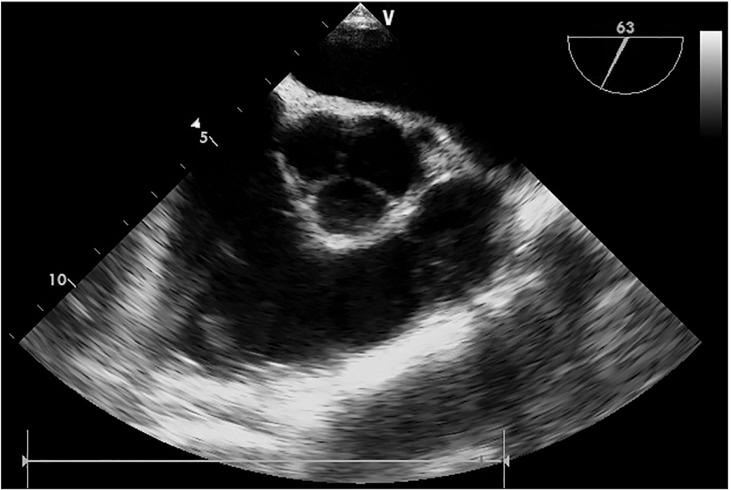

An 81-year-old male patient was scheduled for a laparoscopic cholecystectomy due to acute cholecystitis. About 50 minutes into the operation, the arterial blood pressure suddenly decreased and ventricular fibrillation appeared on the electrocardiography. The patient received cardiopulmonary resuscitation and recovered a normal vital sign. We suspected a carbon dioxide embolism as the middle hepatic vein had been injured during the surgery. We performed a transesophageal echocardiography and were able to confirm the presence of multiple gas bubbles in all of the cardiac chambers. After the operation, the patient presented a stable hemodynamic state, but showed weaknesses in the left arm and leg. There were no acute lesions except for a chronic cerebral cortical atrophy and chronic microvascular encephalopathy on the postoperative brain-computed tomography, 3D angiography and magnetic resonance image. Fortunately, three days after the operation, the patient's hemiparesis had entirely subsided and he was discharged without any neurologic sequelae.

一名81岁男性患者因急性胆囊炎计划接受腹腔镜胆囊切除术。手术进行约50分钟时,动脉血压突然下降,心电图显示出现心室颤动。患者接受了心肺复苏,生命体征恢复正常。我们怀疑是二氧化碳栓塞,因为手术中肝中静脉受到了损伤。我们进行了经食管超声心动图检查,证实所有心腔内均存在多个气泡。术后,患者血流动力学状态稳定,但左侧手臂和腿部出现无力症状。术后脑部计算机断层扫描、三维血管造影和磁共振成像显示,除慢性脑皮质萎缩和慢性微血管脑病外,无急性病变。幸运的是,术后三天,患者的偏瘫完全消退,出院时无任何神经后遗症。